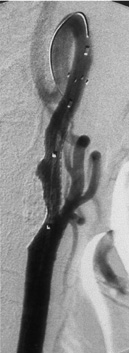

The carotid arteries are the two large blood vessels at each side of the neck. When the arteries become narrow or blocked, the lack of blood flow and oxygen to the brain can cause a stroke. Harlan had blockage in both carotid arteries (nearly 90 percent on one artery and 80 percent on the other artery), and ended up having two stents (wire mesh tubes) inserted — one in each artery — within two months. The stents help to keep the blocked arteries open in much the same way as a balloon is used in angioplasty to open a blocked coronary artery.

Traditional surgery would have involved an incision into the neck to open the carotid artery, as well as a longer in-hospital stay and recovery time. Instead, Dr. Mortazavi inserted a tiny catheter with a collapsed stent (a fine, tubular wire mesh) through a small incision in the groin. Using X-ray imaging, he then guided the catheter up to the blockage in the neck and inflated the stent to restore normal blood flow.

Carotid Artery Blockage & Stents

Carotid artery stenosis – or blockage — occurs when the carotid arteries narrow, usually due to the buildup of fatty materials under the inner lining of the arterial wall. The blockage can cause a sudden loss of brain function (stroke). The risk of stroke increases with the degree of blockage. Generally, surgery is recommended if the blockage is more than 70 percent.

With minimally invasive procedures, there is no incision in the neck or the artery. Instead, the collapsed stent is inserted through a small incision in the leg. Benefits include a shorter hospital stay (within 24 hours), faster recovery, and no large incision or scar.

For years, the only way to repair a blockage in one or both of the carotid arteries was traditional open surgery involving a large incision in the neck. With the new, minimally invasive procedure, the stent is inserted endovascularly (within the blood vessel) through a small opening in the groin.

This less invasive procedure benefits patients with serious medical conditions who are at higher risk for surgery. The physician inserts a fine wire, which travels inside the catheter, and guides it to a point beyond the lesion (blockage). The wire has an umbrella-like filtration tip that provides protection from floating debris. Once the filtration device is in place, the stent is expanded. The stent holds the artery open, restoring the blood supply and helping to prevent the risk of stroke in the future.